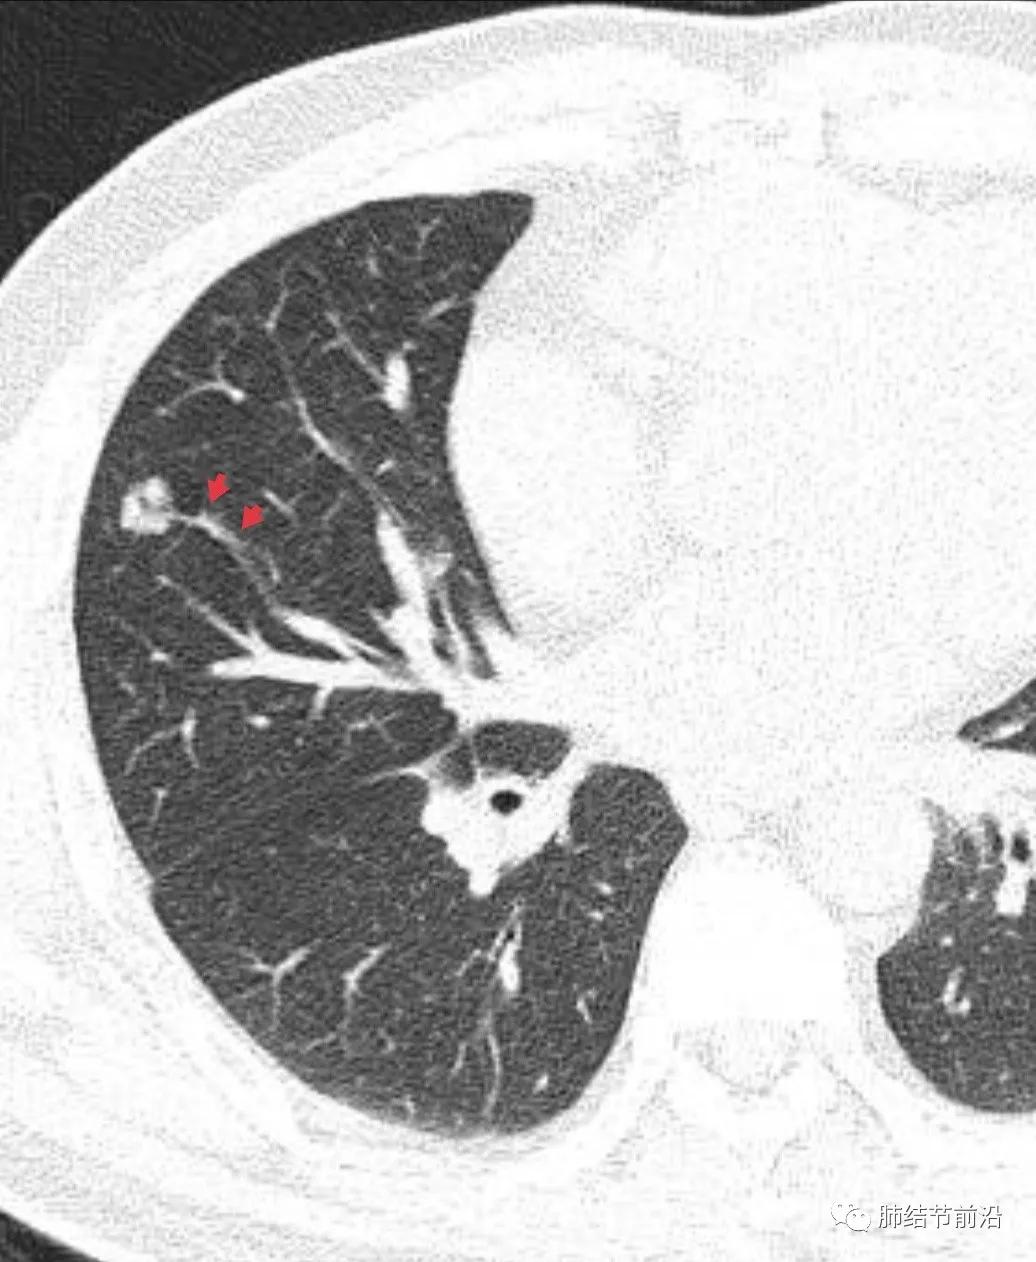

肿瘤组织需要氧供,新生血管是肿瘤的特征之一。传统的鉴别肺结节良恶性的标准之一就是血管集束征。然而在磨玻璃结节释放的血管生成因子并不强烈,新生血管不明显。则表现为诱导血管弯曲,出现明显有别于正常血管的弯曲现象,并向结节生长,称之为"血管弯"。这是肿瘤性磨玻璃/半实性结节很常见的特异性现象,出现这种表现,诊断磨玻璃/半实性结节为早期肺癌十拿九稳。“血管弯”名词引用自武汉市人民医院谭先华主任。

病例3